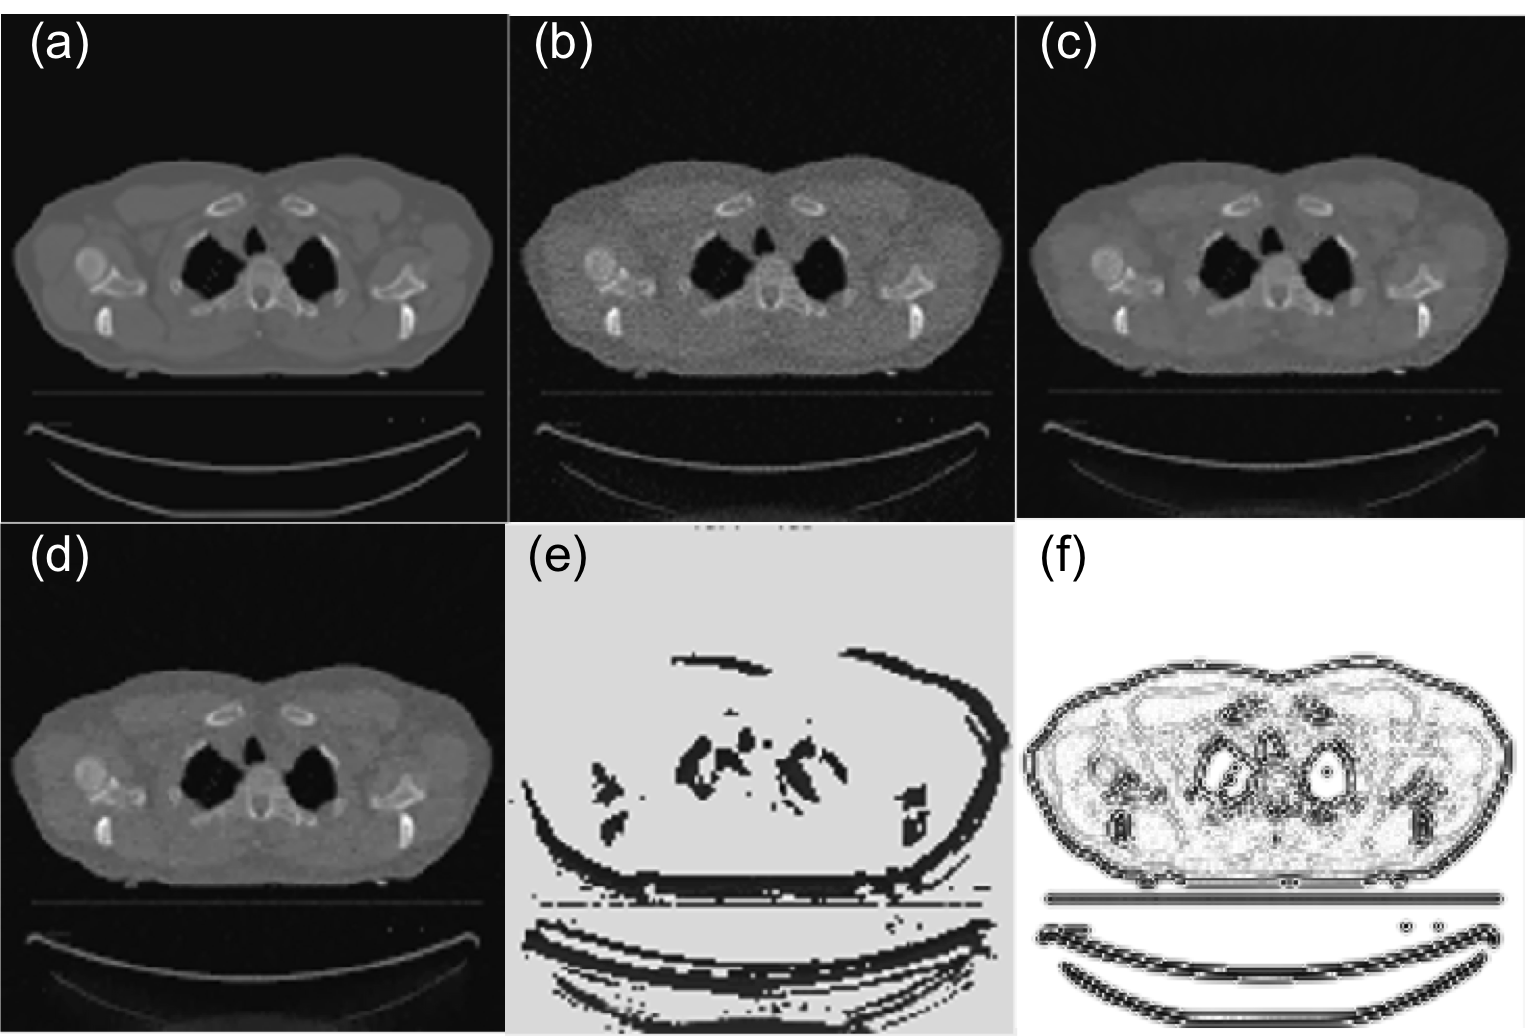

Fig. 6 is a case that is used in training, whereas Fig. 7 is the same one in Fig. 5, which is not included in training. Since we arbitrarily set initial values of , which is too small in these two cases, the resulting images contain a lot of noise (Fig. 6(b) and 7(b)). After the parameter is tuned by PTPN, the image quality in both cases is substantially improved (Fig. 6(c) and 7(c)).

We compare the results with those under manually tuned parameters. Since it is impractical for one to adjust the parameter for each individual pixel, we consider a special context that the parameter is a constant throughout the image and we manually adjust this parameter value for the best image quality. The appropriate parameter values are for Fig. 6 and for Fig. 7. Fig. 6(d) and 7(d) depict images reconstructed under these parameters in the two cases, respectively. It is found that the images still contain a certain amount of noise and the quality is inferior to those with parameters tuned by PTPN.

As for the parameter maps tuned by the PTPN shown in Fig. 6(e) and 7(e), it is observed that PTPN deliberately reduces parameter values most around image edges. This is understandable. Reducing parameters at those pixels decreases the amount of regularization in those areas, which is beneficial in terms of preserving image edges.

Interestingly, for the simple problem in Eq. (2), it is possible to derive the optimal parameter map . As such, let us take the gradient of the objective function and set it to zero at : . This implies that the optimal parameter map is

The numerator in this expression is more or less an image of noise that is obtained by back-projecting the residual error in the projection domain to the image domain. Here, we neglect the image structure of the noise and plot the image in Fig. 6(f) and 7(f) for the two cases, respectively. The images shows that is small along the image edges. Comparing subfigures (e) and (f) in Fig. 6 and Fig. 7, the similarity between corresponding pair of images implies that PTPN can intelligently adjust towards the optimal parameter maps. Note that this intelligence is purely developed by the PTPN itself through the reinforcement learning process. Except providing rewards for an action, we do not explicitly give any information regarding how to tune the parameters.